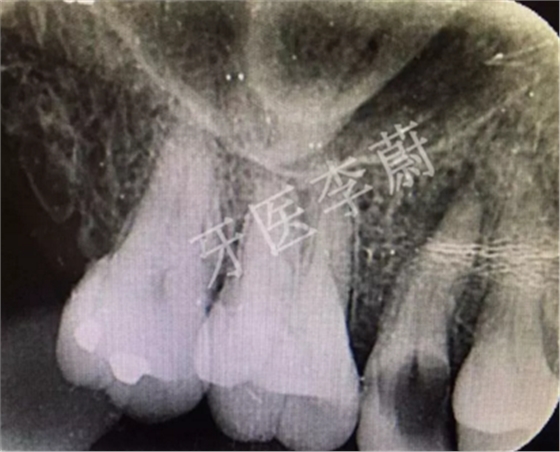

局部X牙片

X片示:15殘冠影,根尖有骨密度降低影。

15牙根管預(yù)備試尖片